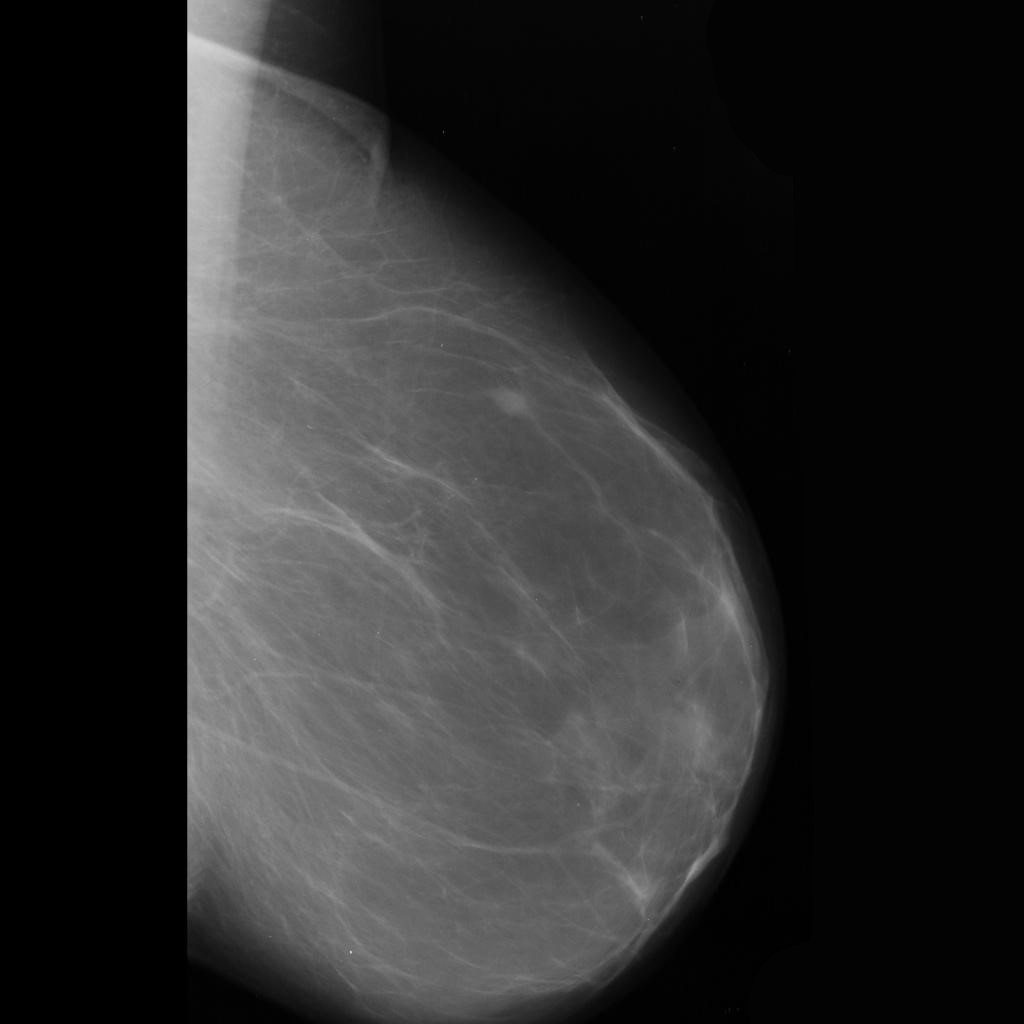

benign